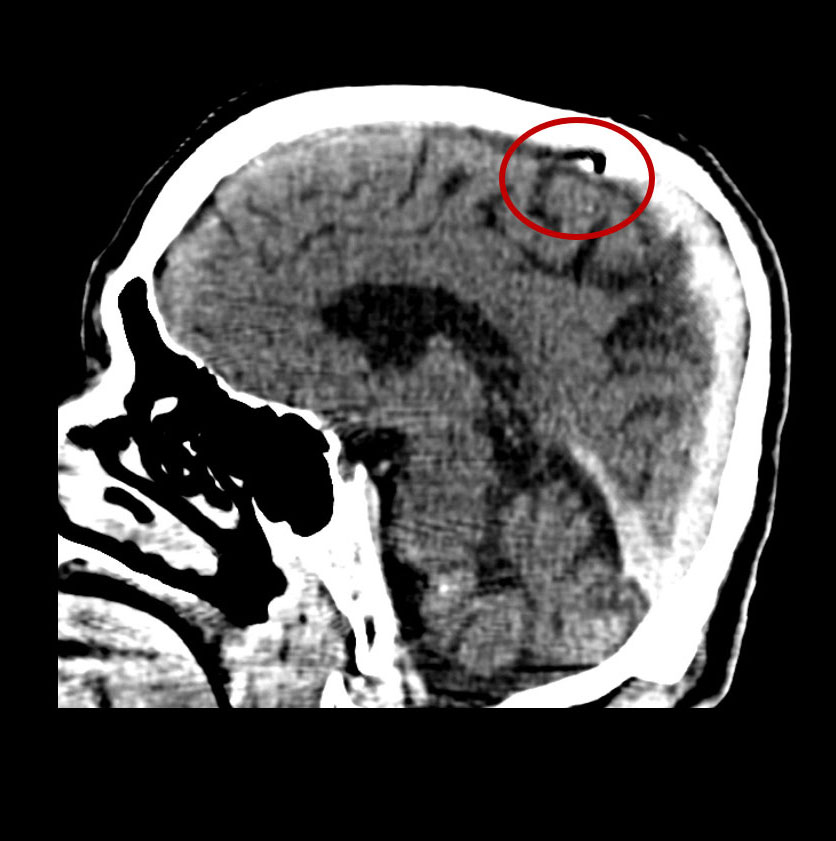

Non-contrast CT Brain:

Focus of air in the superior sagittal sinus

CT Brain:

- Linear or punctate air foci within cortical sulci or cerebral vessels.

- Air outlining cortical arteries or dural venous sinuses.